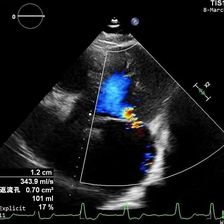

近日,四川省人民医院心脏超声与计算心脏病学团队、结构性心脏病团队于《Quantitative Imaging in Medicine and Surgery》分享的病例,通过多模态超声精准识别舒张期二尖瓣与三尖瓣反流,并成功通过希氏束起搏实现血流动力学逆转,为临床提供了宝贵的诊断与治疗思路。